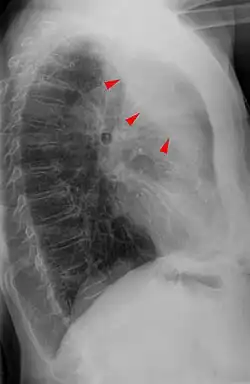

Bei der Perkussion hört man eine Dämpfung des Lungenschalls. Bei der Palpation besteht eine Abschwächung des Stimmfremitus.[3] Das Atemgeräusch ist bei der Auskultation der Lunge abgeschwächt. Im Röntgenbild des Thorax sind als direkte Zeichen eine Transparenzminderung und Verlagerung der Lappenspalten sowie als indirekte Zeichen ein Zwerchfellhochstand, eine Mediastinalverlagerung, ein kompensatorisches Emphysem, eine Hilusverlagerung und eine Engstellung der Rippen zu sehen. Differenzialdiagnostisch muss an eine Pneumonie gedacht werden, Atelektasen zeigen im Gegensatz zu dieser kein Bronchopneumogramm. Alternativ oder ergänzend zum Röntgenbild kann man eine Computertomografie-Aufnahme anfertigen. Im Ultraschall sieht man Atelektasen im Bereich eines Pleuraergusses als nicht belüftete, volumenverminderte Lungenabschnitte.